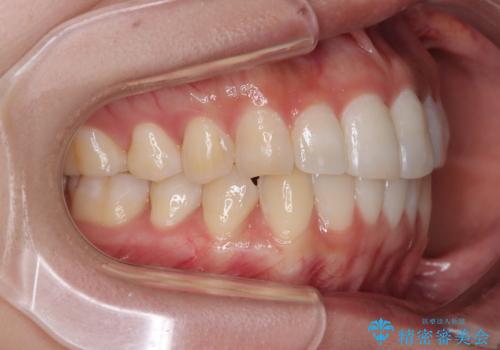

前歯のデコボコを治したい インビザライン矯正

- 上下前歯の叢生を気にして来院された患者様です。

インビザラインでの治療を希望されていて、デコボコの程度が中等度であり、安価なパッケージにて対応可能と判断されたため、インビザライン・モデレートを用いて矯正治療を行うこととしました。